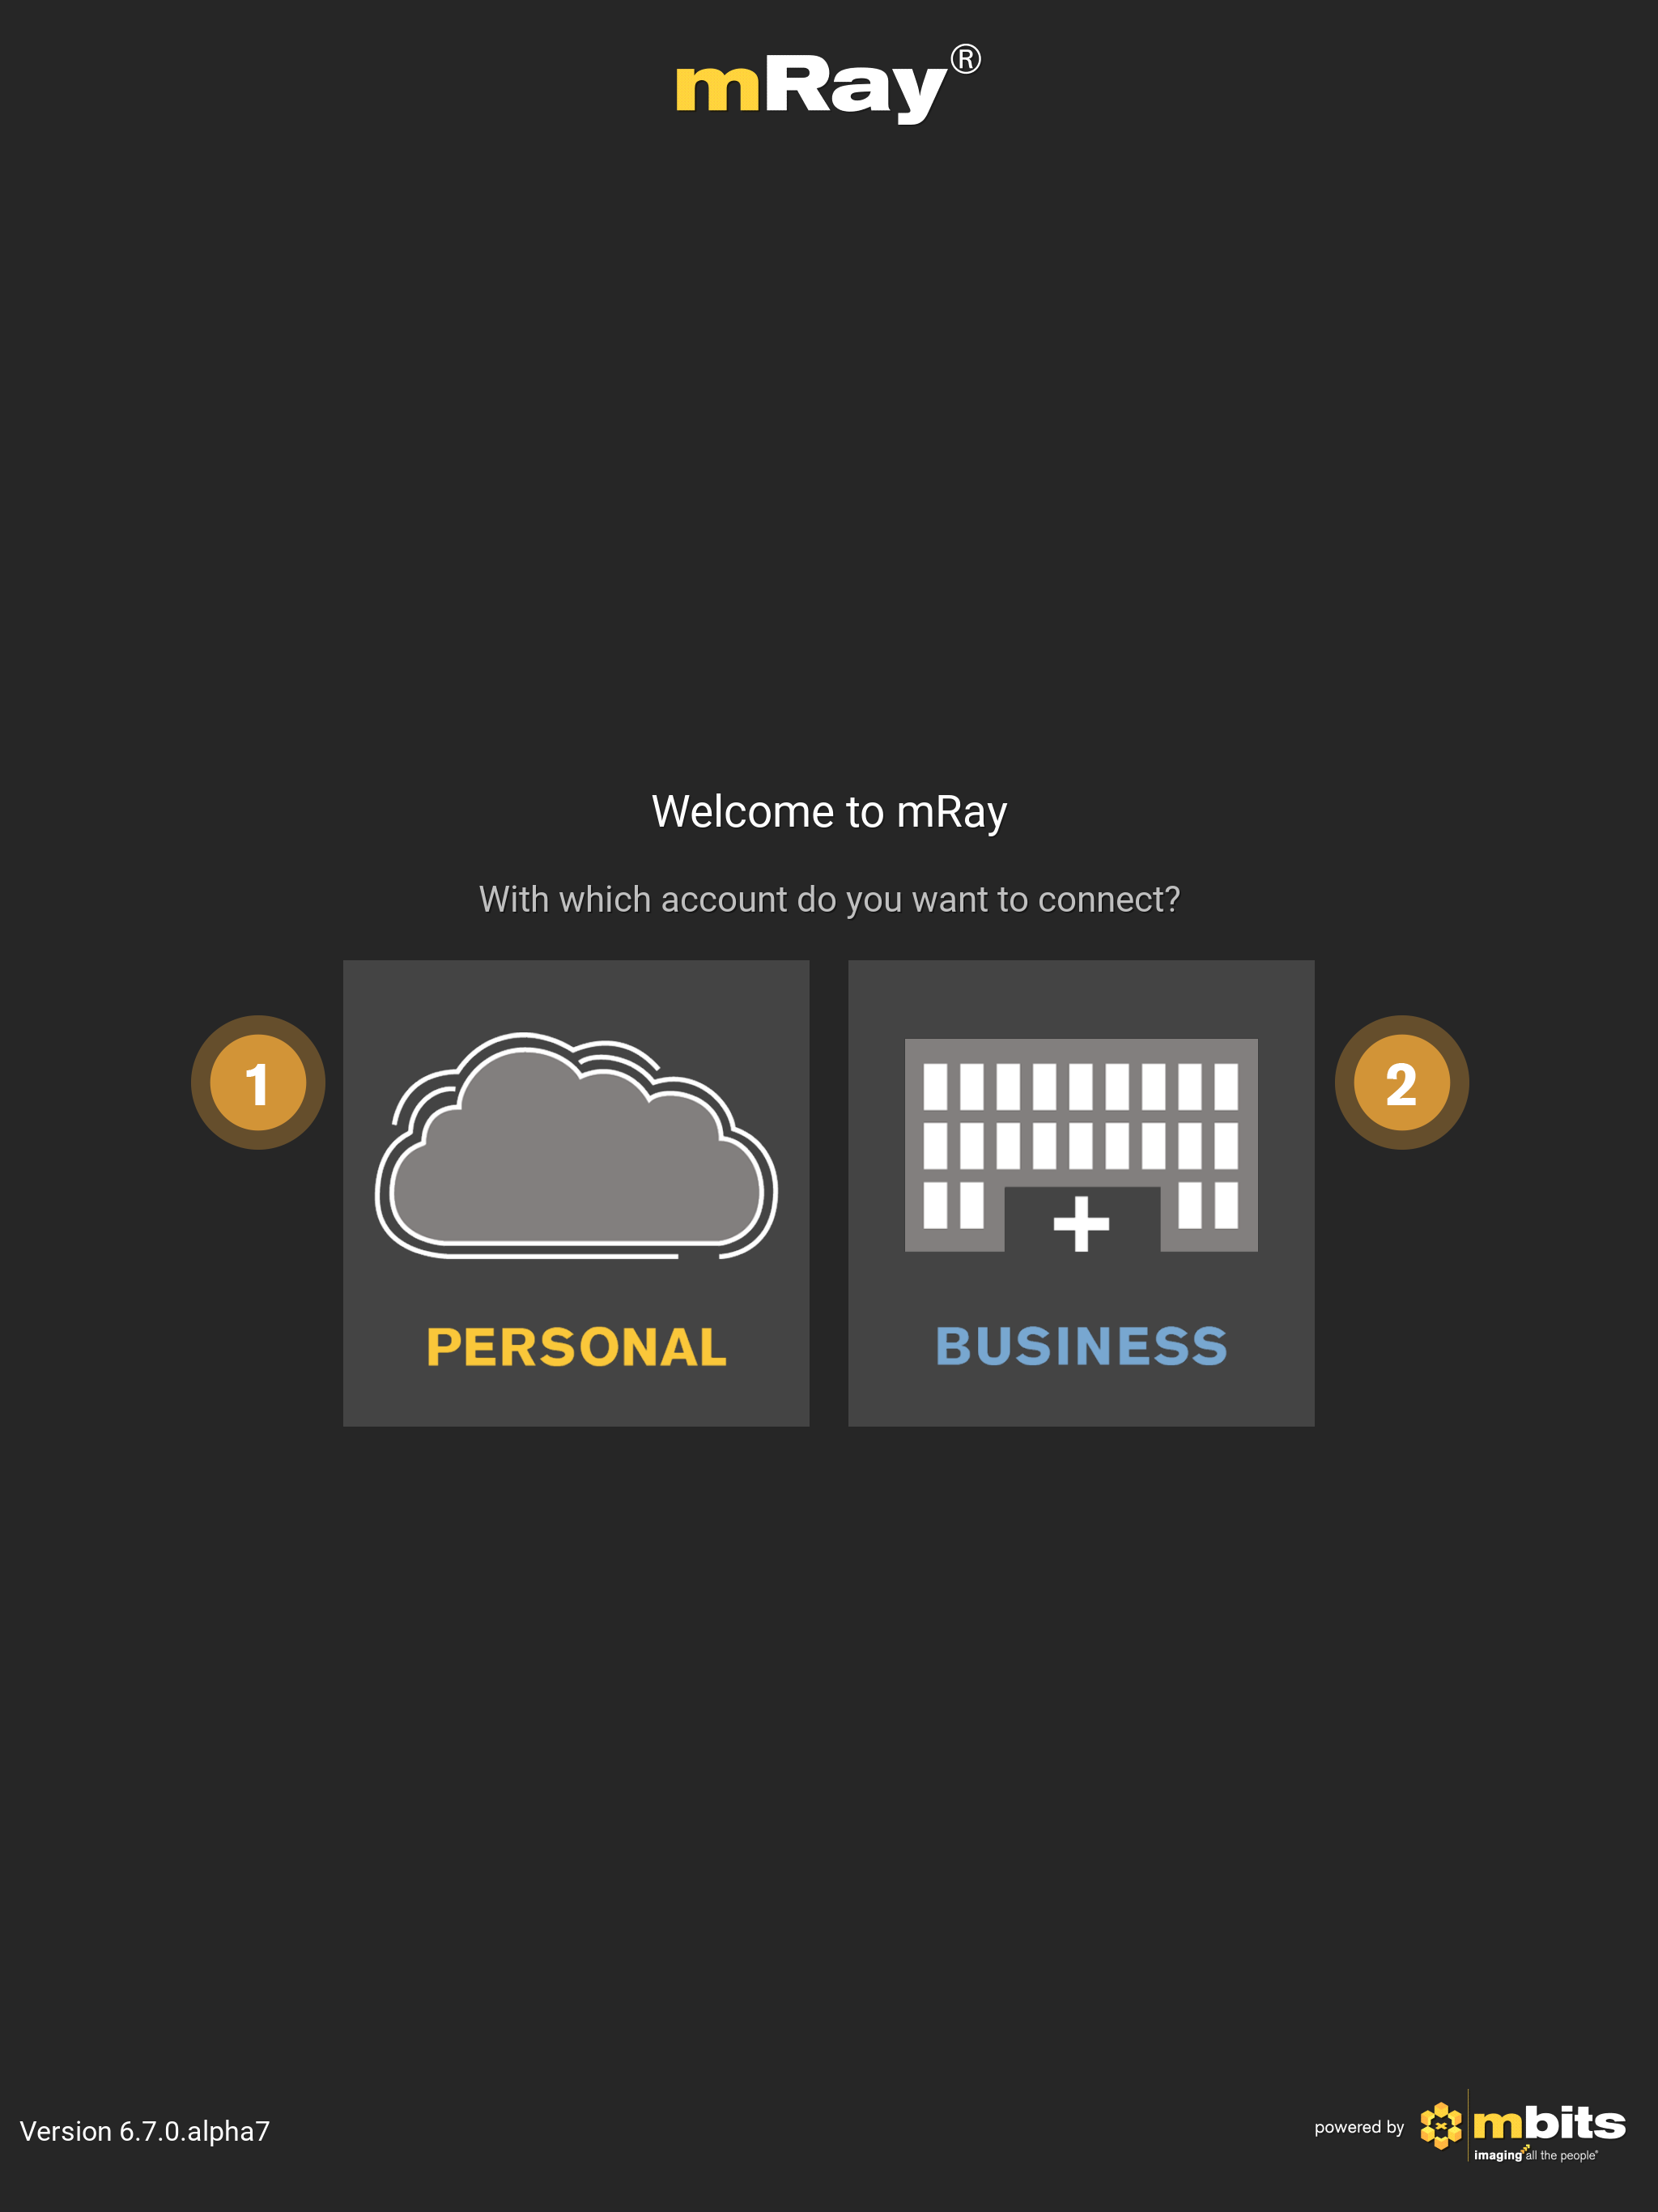

8.1. Welcome screen

The welcome screen appears as soon as the application has been started (Loginscreen). After deciding whether or not the cloud service should be used, additional text fields for username and password will appear. In the next screen you can then enter your credentials to proceed into the application (see Cloud Login or Own server login). If the login data is correct you will be directed to the main screen of the application. Enter your login credentials to log in.

-

mRay Cloud: Use a hosted mRay Server, where you can register and upload your own DICOM data.

-

Own mRay Server: Use a mRay Server hosted by your clinic.